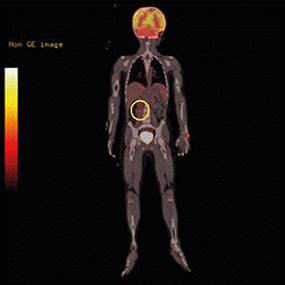

For more detailed examination, magnetic resonance imaging (MRI) was taken. An arterial T1-weighted MRI showed a lobulated mass measuring 3.6×3.8 cm, with high signal intensity, in the right suprarenal area (Fig. 2). Positron emission tomography (PET)-computed tomography (CT) showed hypermetabolism in the right adrenal gland and suggested the need to clarify whether this is a metastatic lesion at the anterior aspect of right psoas muscle (Fig. 3).

Fig. 3

Positron emission tomography-computed tomography. The round circle indicates a hypermetabolic lesion on the right psoas muscle. This lesion was suspicious of metastasis of ganglioneuroblastoma. Multi-disciplinary teams discussed the lesion and concluded that metastasis was not definite.